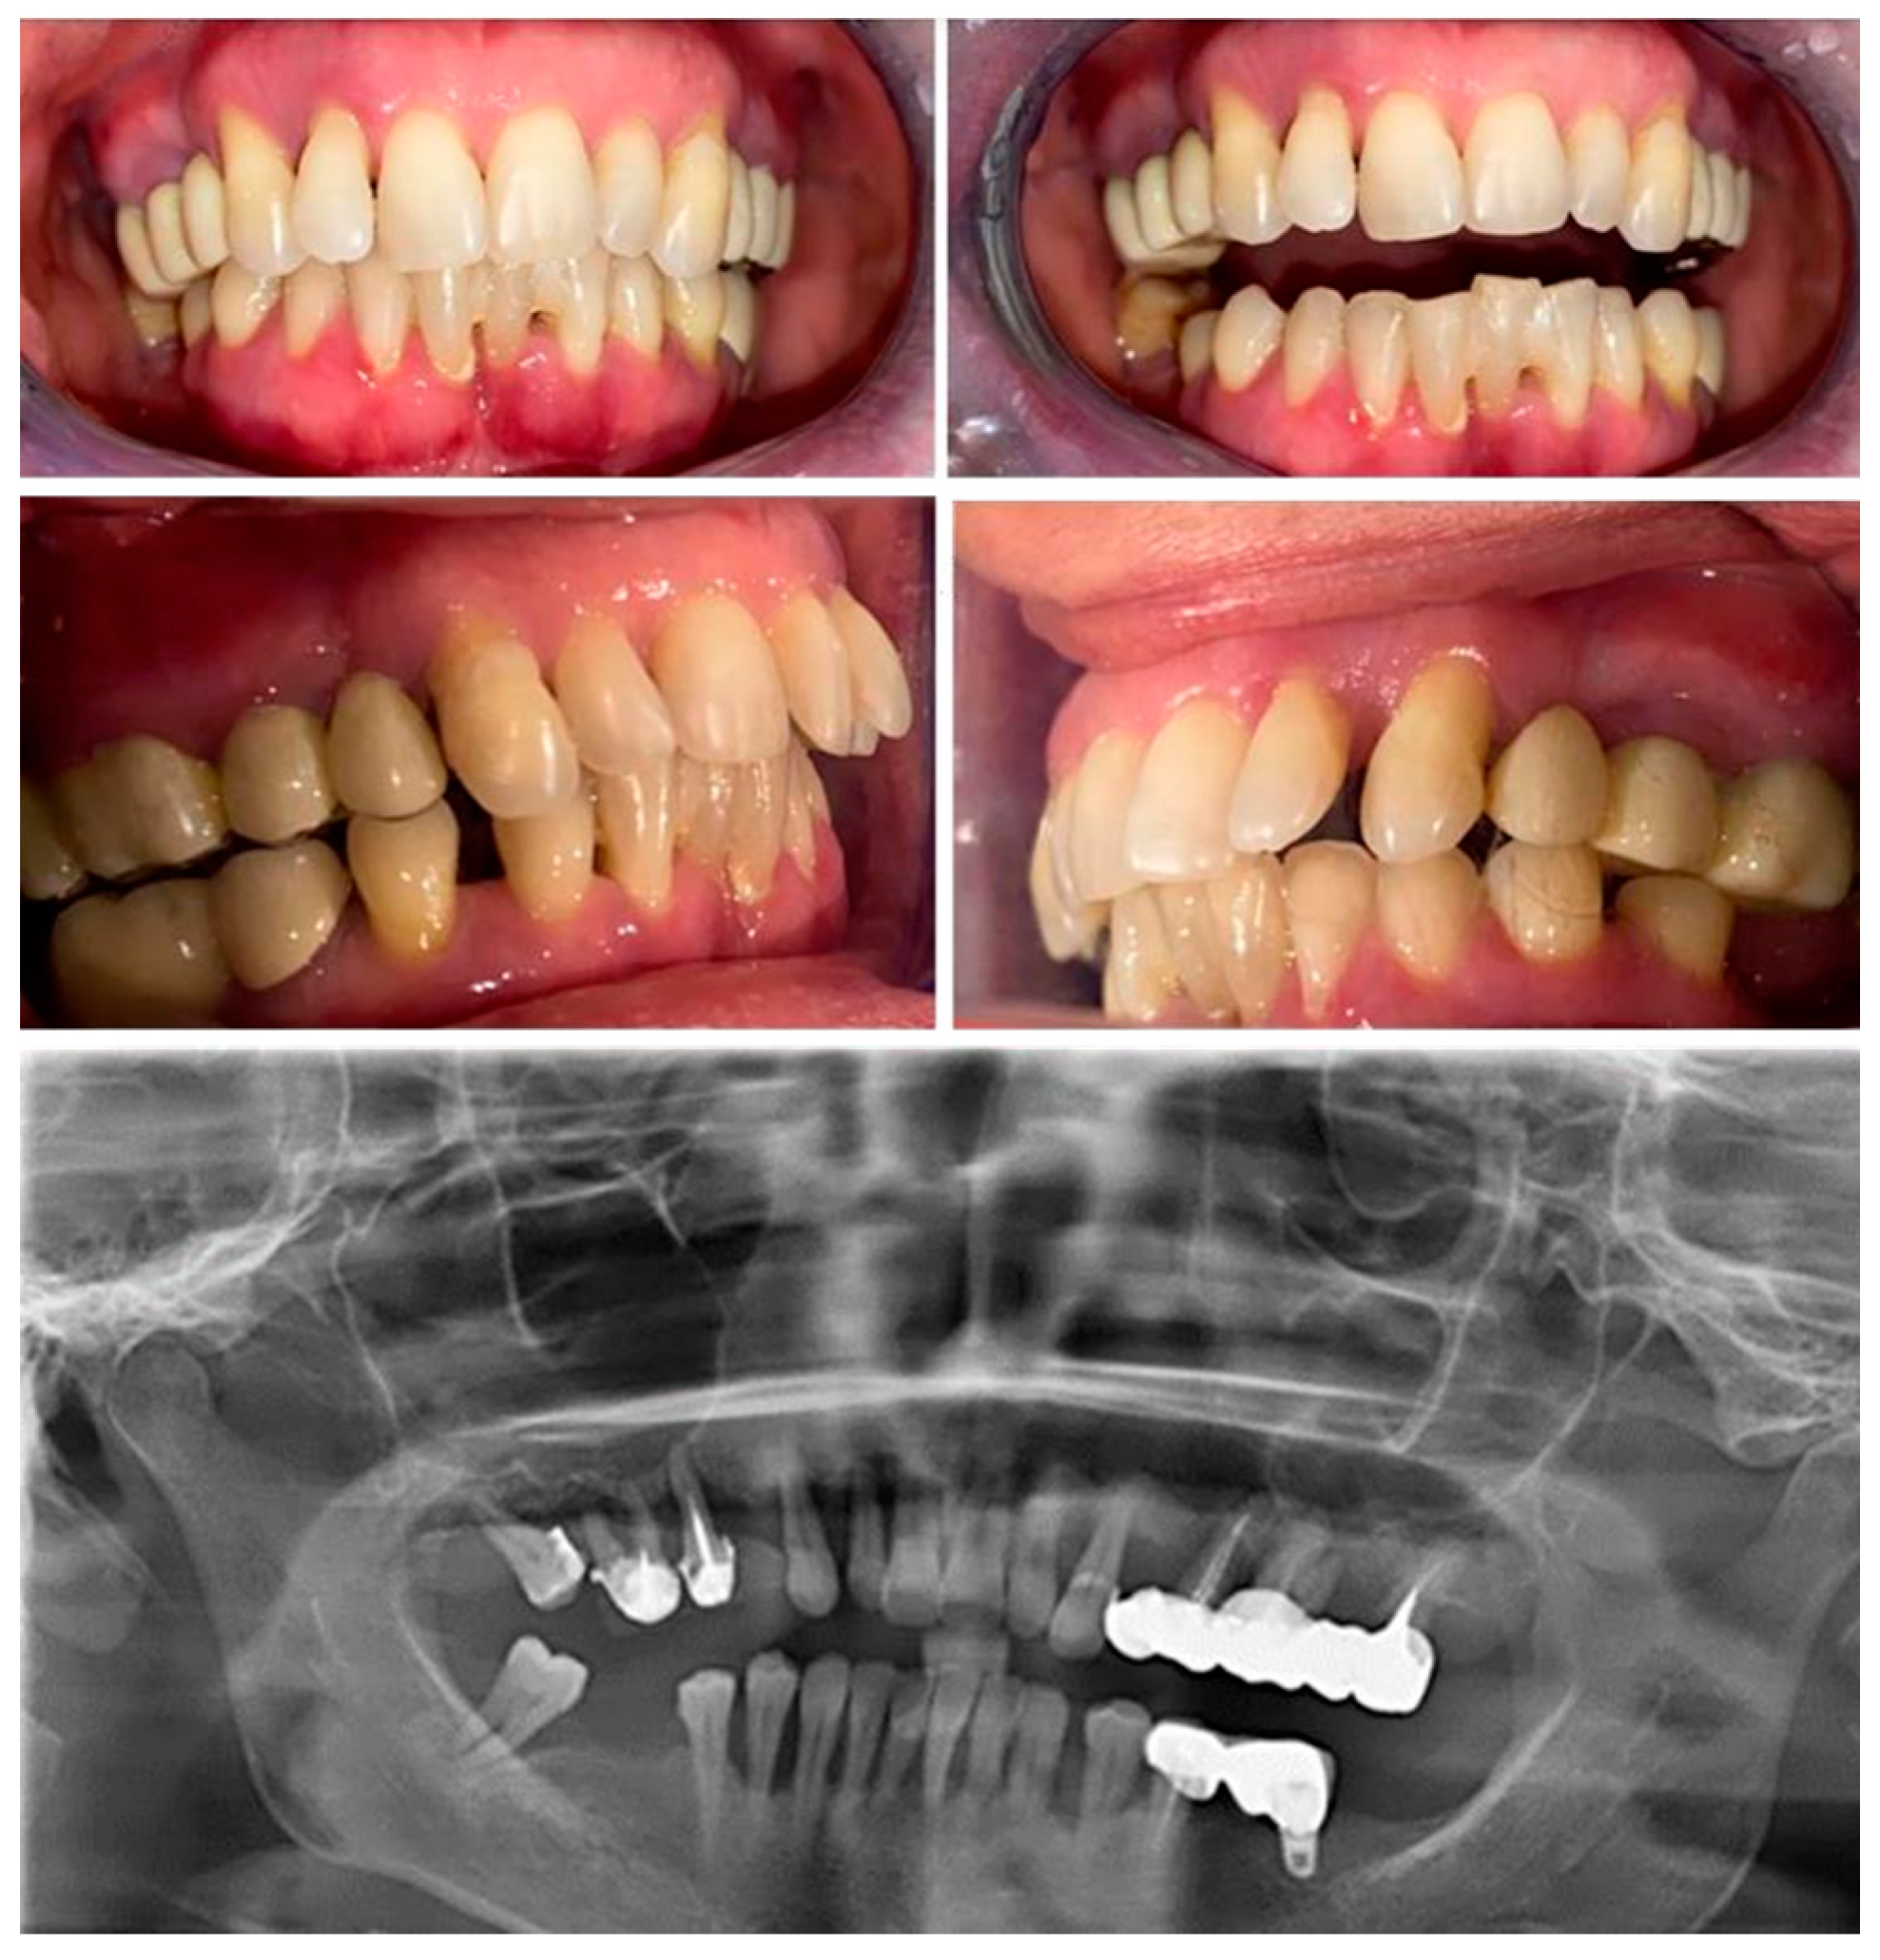

The patient has no history of periodontal treatment. The periodontal changes are also encountered in the case 2 of a 47-year-old woman (Figure 3). Medical analyses revealed a deficiency of vitamin D, which was also noted to be untreated. Serum calcium levels remained unchanged. The first appointment was prompted by similar concerns as in case 1, regarding the poor aesthetic appearance of the gums, tooth mobility, and misalignment, along with additional issues related to chewing difficulties.

Figure 3.

Case 2 - Clinical and radiological aspects.

The initial examination revealed deep probing pocket depths, tooth mobility, bleeding upon probing, radiographic bone loss, gum recession, and signs of gingival inflammation (Figure 3 and Figure 4). The plaque index score registered were 23%, radiographic bone loss 65% (more than half of the tooth's root) and bleeding upon probing index (BOP) were 68%. The initial probing depth (PD) was 8 mm at the both maxillary canine and incisors and 9 mm at the mandibular canine and first premolars. The tooth mobility (Miller Classification) was class 2 for maxillary first premolar and molar and class 3 for right maxillary lateral incisor. The diagnosis was periodontitis stage III, grade C. Stage III of periodontitis, in this case, was defined based on the severity (radiographic bone loses extending to the apical third of the root) and probing depth > 6 mm, vertical and horizontal bone loss). The grade of periodontitis was estimated with evidence of bone loss/age > 1.0 [25,26].

The patient had a history of periodontal treatment. The diagnosis of periodontal disease was made six years ago during the initial visit by a general dentist. The treatment followed, consisted of initial periodontal therapy including antimicrobial treatment, subgingival debridement and additional a composite splint was applied to the lower mandibular incisors due to increased mobility Additionally, the patient presented with fixed prosthetic supported by dental abutments in the maxilla as well as dental and implant support in the mandible, which were performed 4-5 years ago.